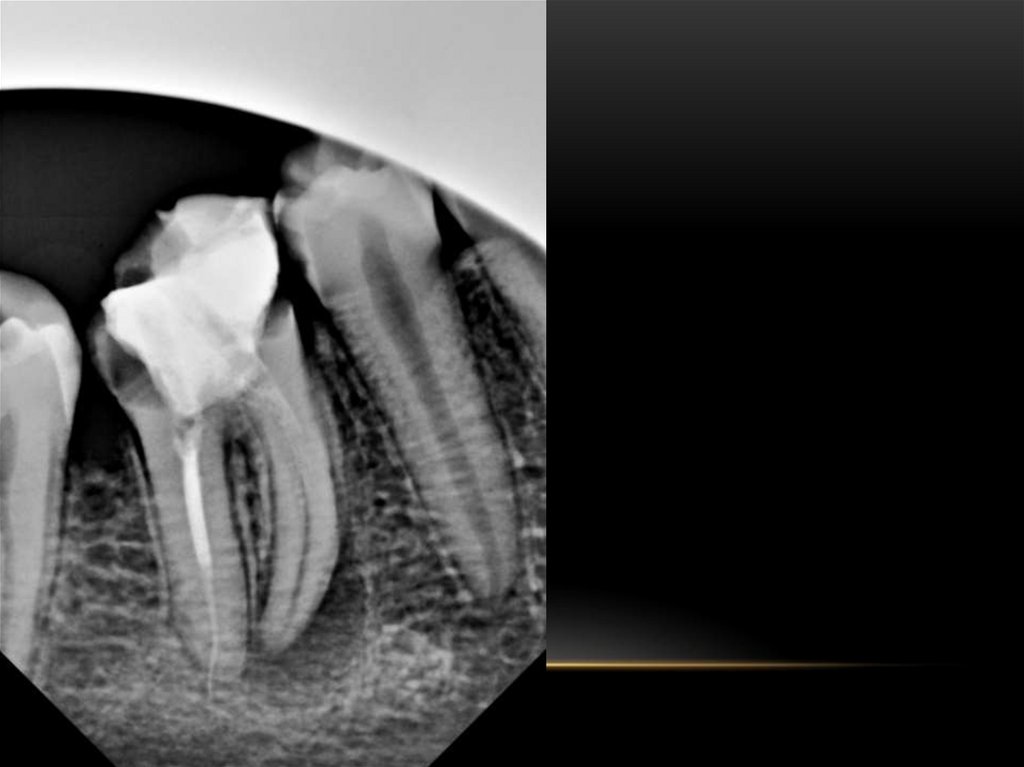

Методики пломбирования корневых каналов

Материалы для пломбирования корневых каналов

Пломбирование корневых каналов зуба

Анатомия корневых каналов

Лечение корневых каналов